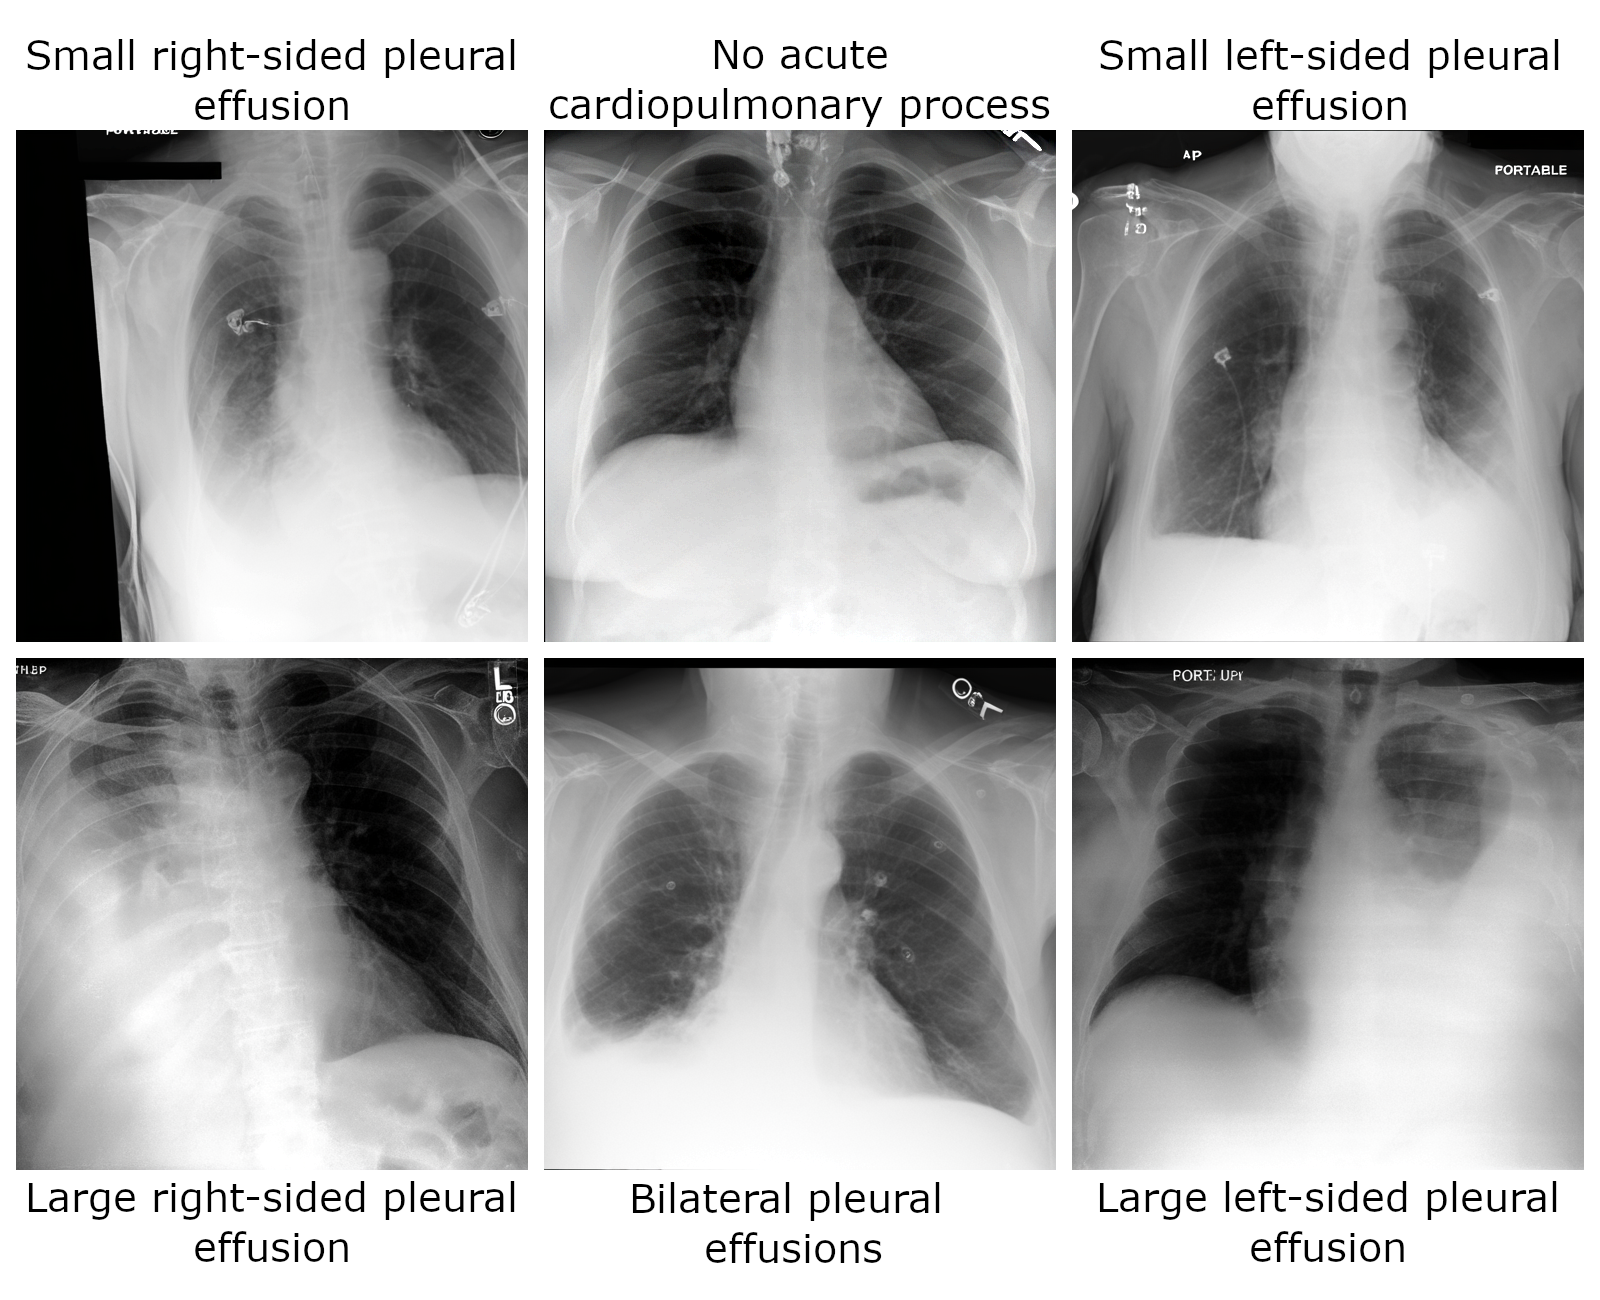

Sampling Chest X-Rays

The generation pipeline can be used to sample images via the following

import torch

prompts = [

"Small right-sided pleural effusion",

"No acute cardiopulmonary process",

"Small left-sided pleural effusion",

"Large right-sided pleural effusion",

"Bilateral pleural effusions",

"Large left-sided pleural effusion",

]

torch.manual_seed(0)

images = generation_pipeline(

prompts,

num_inference_steps=100,

guidance_scale=7.5,

).images